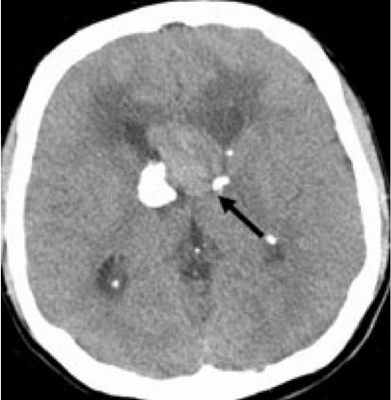

КТ головного мозга при туберозном склерозе. Видны кальцинированные субэпендимальные узелки в стенках боковых желудочков.

Субэпендимарные кальцификаты и корковые туберсы на КТ головного мозга ребенка с туберозным склерозом

Субэпендимарные узлы в 10% случаев трансформируются в гиганто-клеточную астроцитому, которые манифестируют обычно между 5 и 10 годами жизни, имеют тенденцию к росту и локализуются у отверстия Монро

Астроцитома в области отверстий нередко приводит к оккюзионной гидроцефалии.